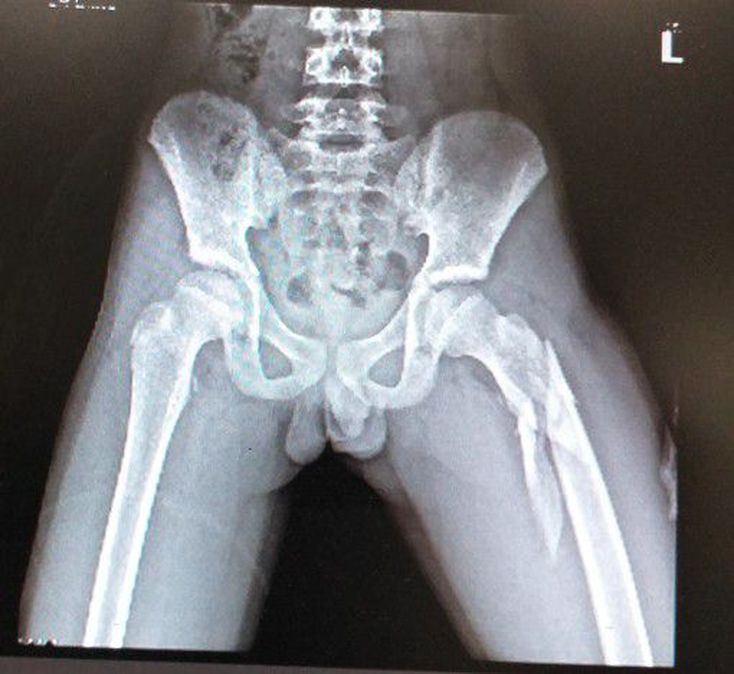

12 year old boy with CA with deformity in lower limb.

Broken femur, ouch

Sub trochantric fracture.

Fracture Head of left femur

Sub trochantric fracture of femur

Nasty oblique comminuted fracture of left femur. That is going to require an ORIF.

Pathological fracture